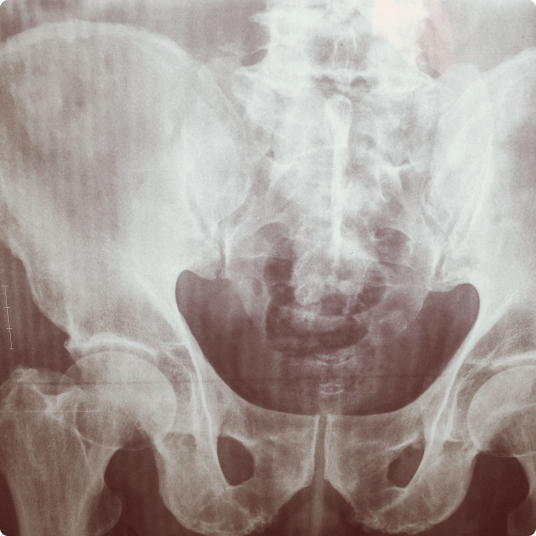

An X-ray image of the pelvis and lower spine, showing bone structure and alignment.

A bone density test uses advanced CT scanning technology to measure the amount of bone mineral in specific areas of your skeleton. This non-invasive test helps determine if you have, or are at risk for, osteoporosis—a condition that makes bones fragile and more likely to break.

Our CT scanner generates precise images of your bones, particularly focusing on areas most prone to fractures, such as the spine and hip.

• Remain still while the scanner captures detailed images of your lower back and hips